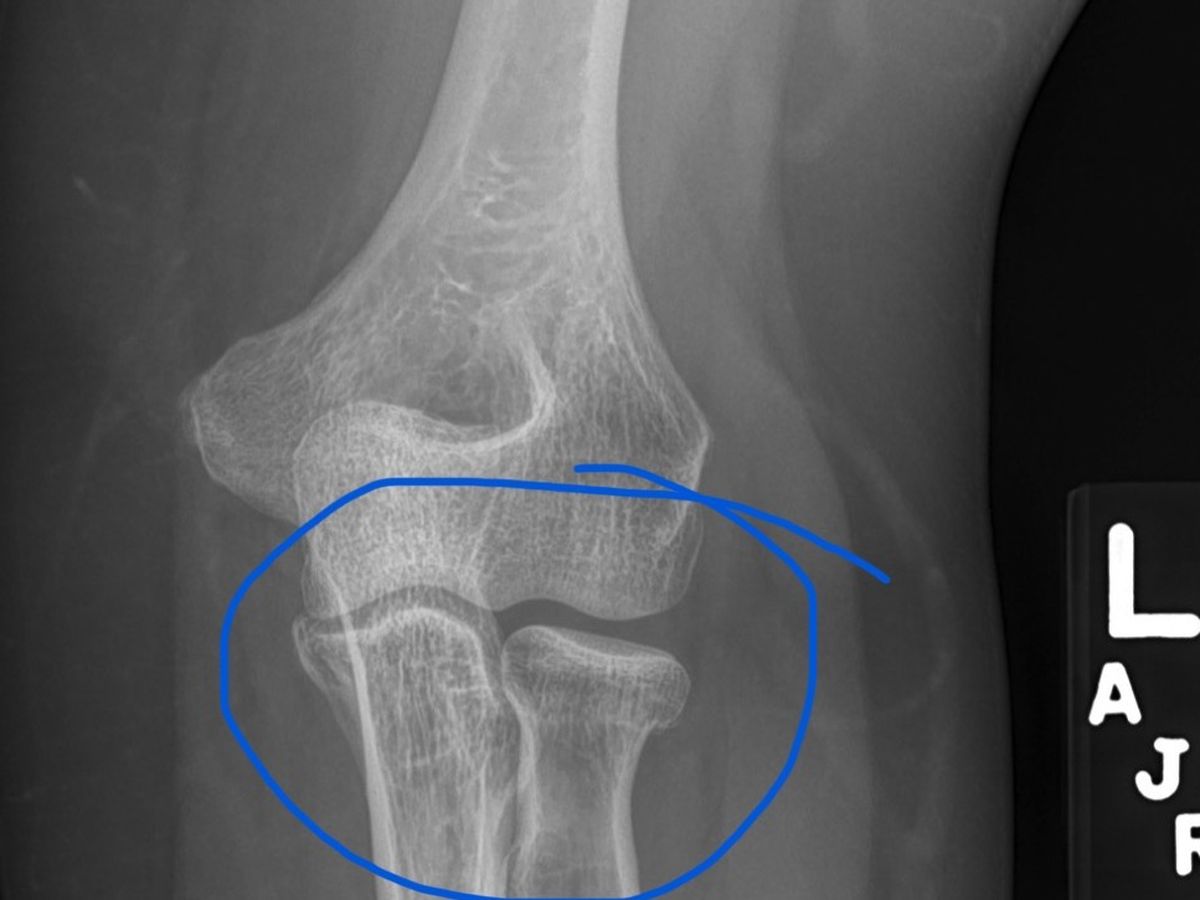

On Sunday, October 6, 2024, I fell and broke my elbow. I have no insurance to cover medical bills, no unemployment, or benefits coming in. I am expected to be out of work for at least 6 months.